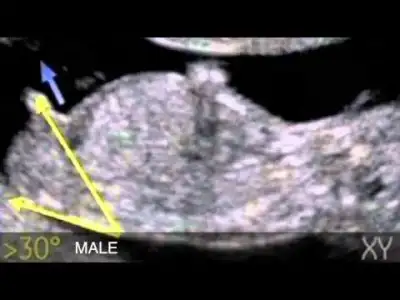

Oh oh kontroller süperYa benim pıtırcık kıpır kıpırdı, ayağını gerip zıplayıp durdu, maşallah ufaklığa.. 2 gün öne geçmiş, doktor folik kestirdi, vitamin verdi hem demir için hem multi hem de d vitamini. 3 hafta sonraya tekrar gideceğim 2 li test için.

Videodan foto aldim net değil ne yazık ki video çekince doktorum foto vermeyi unuttucinsiyet için birşey demedi bir sonrakinde görebiliriz galiba dedi